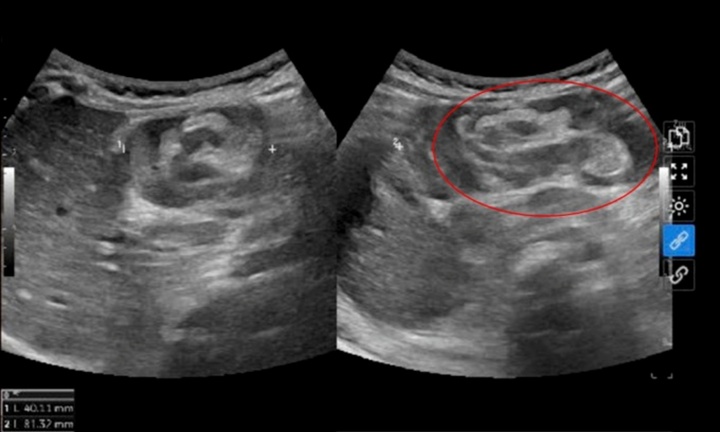

BiVACOR là tên của trái tim nhân tạo hoàn toàn do tiến sĩ Daniel Timms phát minh. Đây là thiết bị bơm máu quay cấy ghép đầu tiên trên thế giới có thể thay thế hoàn toàn tim người, sử dụng công nghệ nâng từ để tái tạo dòng máu tự nhiên của một trái tim khỏe mạnh.

Thiết bị này vẫn đang trong giai đoạn đầu nghiên cứu lâm sàng, được thiết kế dành cho bệnh nhân suy tim giai đoạn cuối ở cả hai tâm thất. Suy tim thường xảy ra do các bệnh lý khác làm tổn thương hoặc suy yếu tim đến mức không thể bơm máu hiệu quả trong cơ thể.

Thiết bị BiVACOR đóng vai trò một cầu nối giúp bệnh nhân duy trì sự sống cho đến khi có tim hiến tặng. Tuy nhiên, mục tiêu dài hạn của BiVACOR là giúp bệnh nhân sống với thiết bị này mà không cần ghép tim.